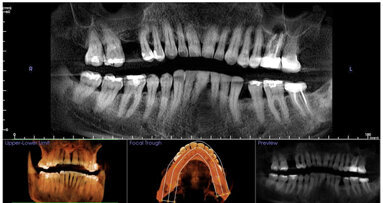

El autor asegura en este artículo que las imágenes tridimensionales que proporciona la tomografía computarizada de haz cónico ...